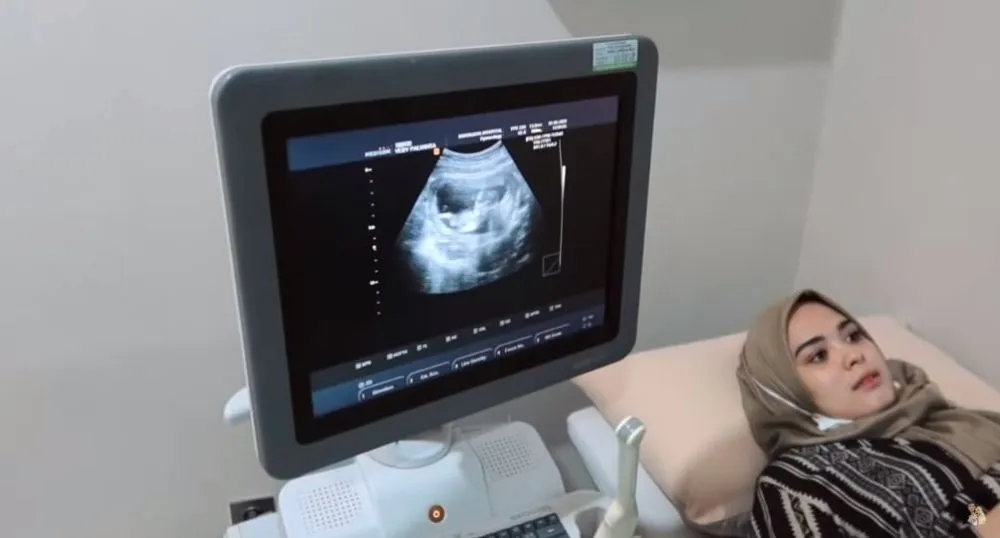

5. Momen Vebby memeriksa kandungan untuk ketiga kalinya. Selalu ingin melihat tumbuh kembang janin.

6. Dokter menjelaskan satu persatu organ tubuh si kecil di dalam gambar USG.